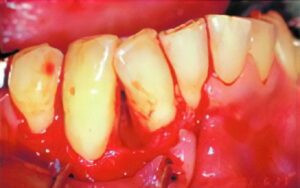

スケーリングだけでは、歯石などが取り切れないなどひどい場合には、ルートプレーニングという方法がとられます。通常、歯石除去には麻酔は使用されませんが、徹底的に歯石を除去する方法であり出血を伴うため、局所麻酔を行います。もっとも、これほどひどくなるには長い年月が必要ですので、通常はスケーリングだけで十分です。